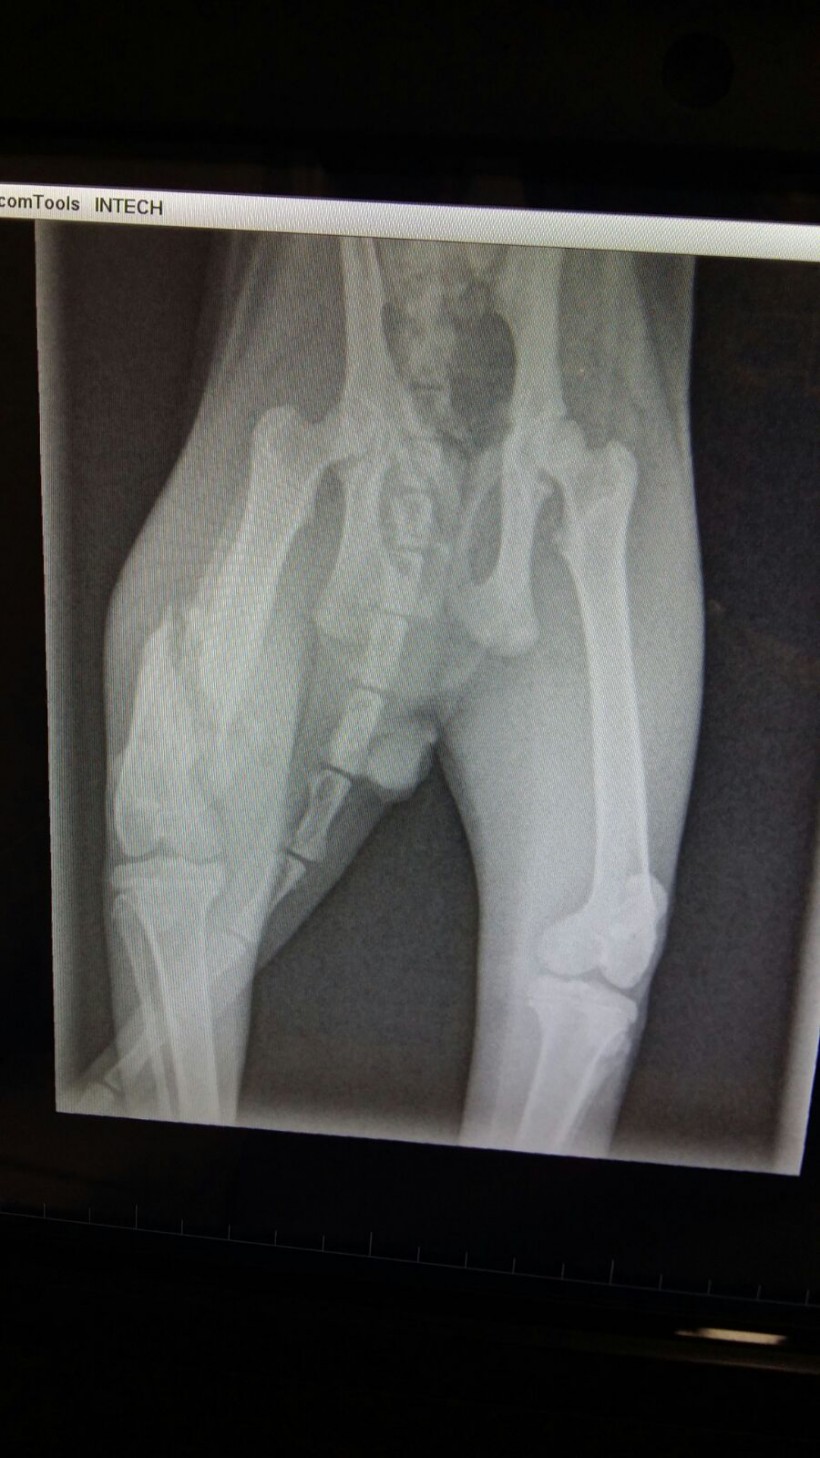

Cris es un gato que tuvo la mala suerte de ser atropellado en la zona del Corte Inglés. Hasta un tiempo después no se encontró, iba vagando sin rumbo y vimos que a raíz del accidente tenía las almohadillas ensangrentadas y una fractura en el fémur. No dudó en ir a los brazos de nuestra compañera Sonia, se dejó coger, cuidar y curar. Al encontrarlo tiempo después del atropello, la fractura que sufre en el fémur a raíz del accidente es una fractura antigua que está haciendo callo y no se puede operar. De momento la fractura va soldándose, pero necesita recuperarse. Ahora está de acogida en casa de Manoli, está muy bien cuidado .